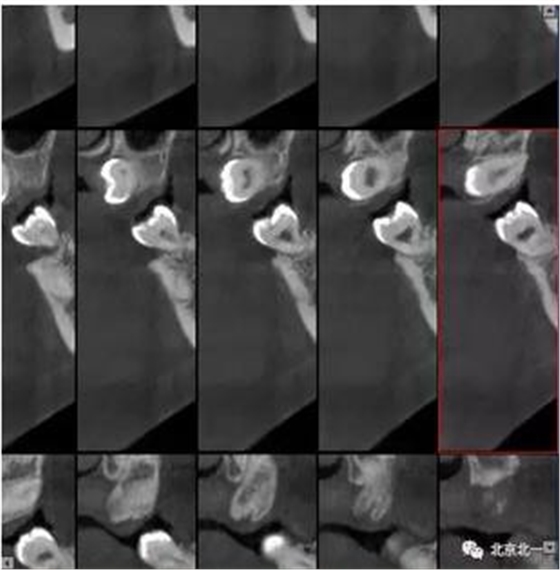

圖三:橫斷面可見智齒水平橫向腭側。完全骨埋伏。

圖四:冠狀面截圖牙根位于唇側,牙冠位于腭側。

圖五:矢狀位截圖可見牙冠截面。